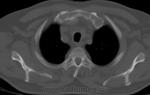

Интереснейший случай был выставлен Татьяной Валентиновной

Наблюдение Татьяны Валентиновны

Так вот,инвалидом он является по псориатическому полиартриту.

Не поверите,но я сам читал диагноз в направлении.Вмешиваться не стал,не в моей поликлинике дело было,просто снимки "стырил".

Первый раз подагрический артрит с таким размахм вижу...

Мне вспомнилось слово мутилирующий.

Изначально подумала на ревматоид, если честно.